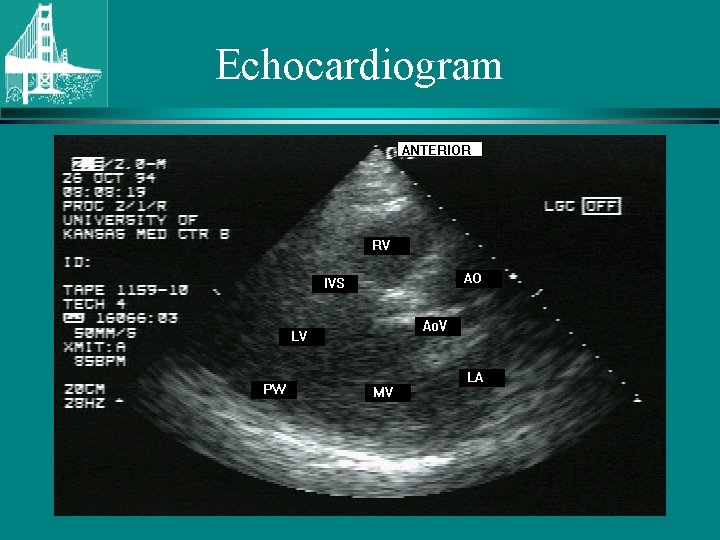

Echocardiogram • • Etiology Valve gradient and area LVH Systolic LV function Diastolic LV function LA size Concomitant regional wall motion abnormalities • Coarctation associated with bicuspid AV © Continuing Medical Implementation …. . . bridging the care gap

Echocardiogram © Continuing Medical Implementation …. . . bridging the care gap